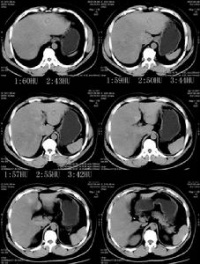

X线检查[编辑 | 编辑源代码]

骨骼显示骨密度普遍降低和佝偻病表现,可见陈旧性骨折腹部平片可见泌尿系结石影和肾钙化。